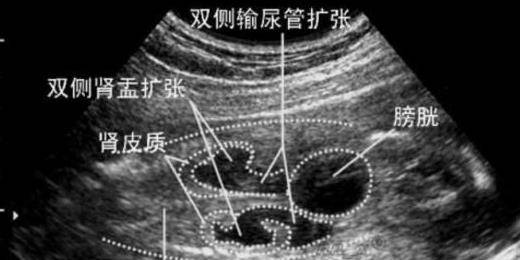

假如孕妈身体出现肾盂分离的状况,大多数是因为胎儿没有大小便引起的,这一班可见是男宝宝身上,不过在下次复查的时候,这种现象便会消失!

通过四维彩超,我们可以得知胎儿是不是有唇裂或者脑部积水,无脑儿,脊柱裂等特殊的结构异常问题,但是对于视力、听觉、智力、先天性遗传等问题,报告没有办法判断出来的!